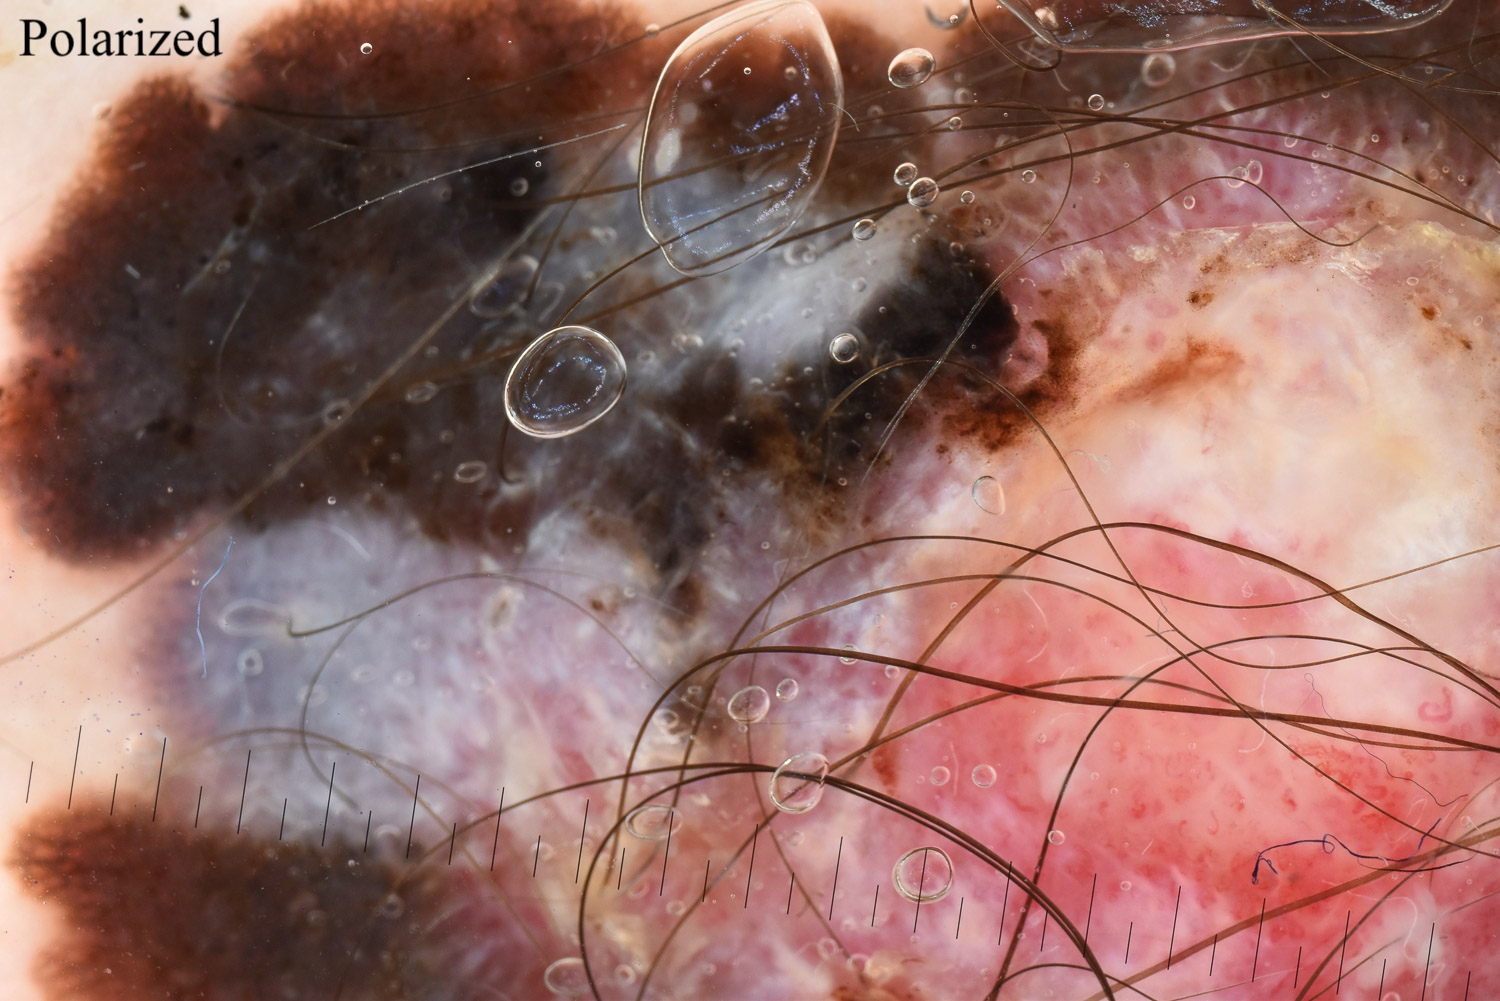

Case: 221